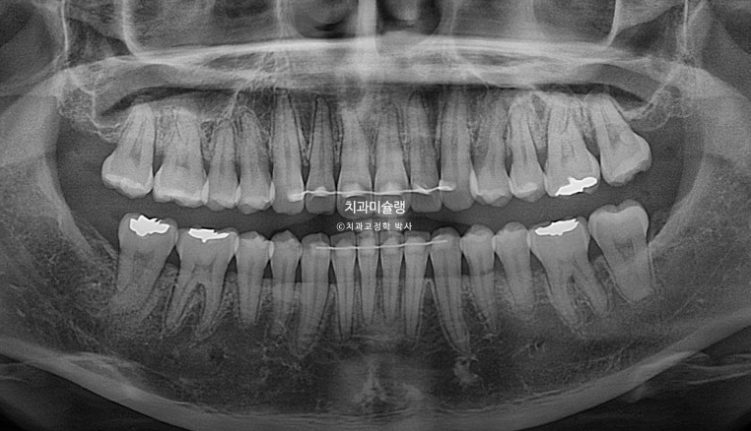

25.11

치근흡수는 없고 치근평행도는 좋습니다.